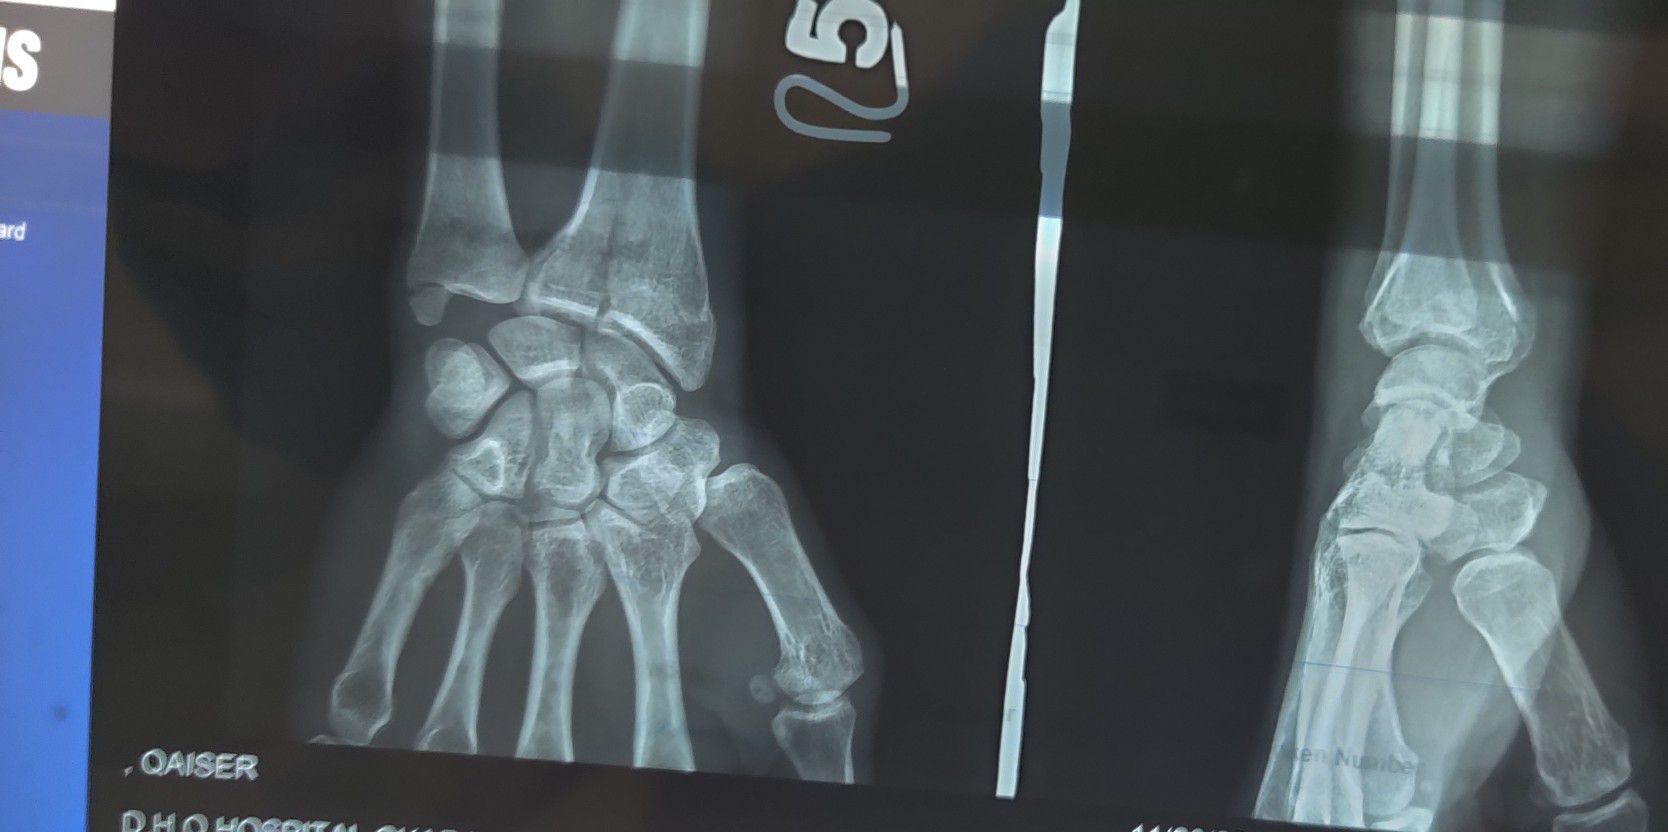

Fracture of Radius

Xray

Orthopaedics

Radius